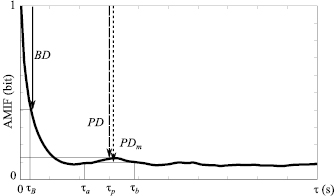

In order to describe HRV complexity during emotion elicitation, the evolution of the information function over the time scale  should be taken into consideration. The AMIF (figure 1) applied to the RR(t) time series was characterized by the following parameters: BD is the beat decay that corresponds with the AMIF decay from

should be taken into consideration. The AMIF (figure 1) applied to the RR(t) time series was characterized by the following parameters: BD is the beat decay that corresponds with the AMIF decay from  s to

s to  s, which represents a standard mean beat period (Palacios et al 2007). Also,

s, which represents a standard mean beat period (Palacios et al 2007). Also,  is the total area under the curve that has been proposed to characterize the morphology, predictability and regularity of the signal (Boettger et al 2008).

is the total area under the curve that has been proposed to characterize the morphology, predictability and regularity of the signal (Boettger et al 2008).

Figure 1. The normalized auto-mutual information function (AMIF) as function of the time scale  . The AMIF value at

. The AMIF value at  represents the entire information of a time series. Beat decay (BD) indicates the AMIF decay over a standard heart beat period (

represents the entire information of a time series. Beat decay (BD) indicates the AMIF decay over a standard heart beat period ( ). Mean peak decay (PDm) indicates the mean information decrease between

). Mean peak decay (PDm) indicates the mean information decrease between  and

and  . Peak decay (PD) indicates the information decay at the maximum peak (

. Peak decay (PD) indicates the information decay at the maximum peak ( ) defined in the interval [

) defined in the interval [ ,

,  ].

].

Standard image High-resolution imageThe AMIF applied to the filtered time series  (t),

(t),  (t) and

(t) and  (t) was characterized by the following parameters:

(t) was characterized by the following parameters:  is the peak decay that shows the information decay at the maximum peak defined in the interval [

is the peak decay that shows the information decay at the maximum peak defined in the interval [ ,

,  ];

];  is the mean peak decay within a time range [

is the mean peak decay within a time range [ ,

,  ] that indicates the mean information decrease between two time lags

] that indicates the mean information decrease between two time lags  and

and  ; and

; and  is the total area under the curve in the same time range [

is the total area under the curve in the same time range [ ,

,  ], where

], where  .

.